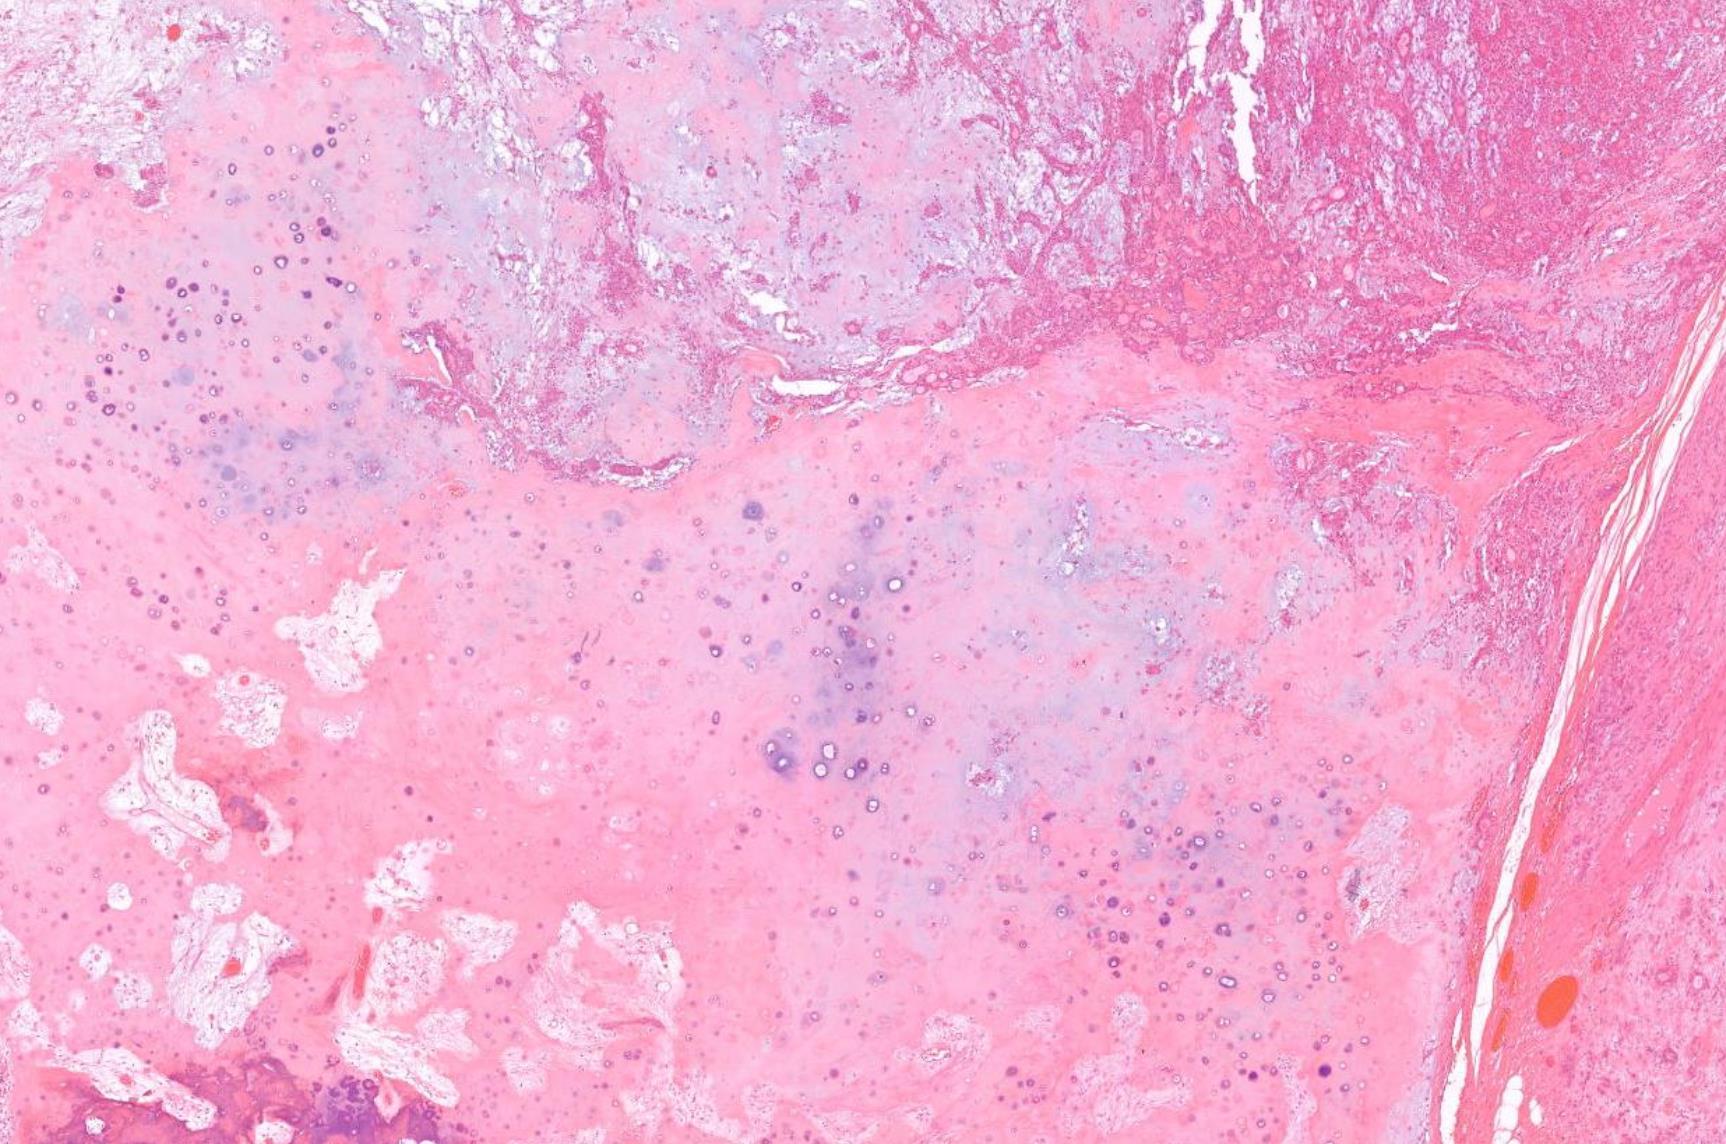

Case 10 66-year-old Excision Of Tumour Tongue / Floor Of Mouth.

??

Case 10 Diagnosis

Mucosal melanoma

• 80% of head and neck MM- nasal cavity, septum, maxillary sinus • In the oral cavity-maxillary gingiva and palate • Flat pigmented lesions • Tumour cells are polymorphic • Lentiginous/pagetoid growth pattern • All head and neck mucosal MM are T3–4 and stage III-IV • T3 Tumour limited to the epithelium and/or submucosa (mucosal disease) • T4a Tumour invades deep soft tissue, cartilage, bone, or overlying skin • Oral pigmented patches DD • Melanotic macule • Smokers melanosis • Amalgam tattoo • Naevi